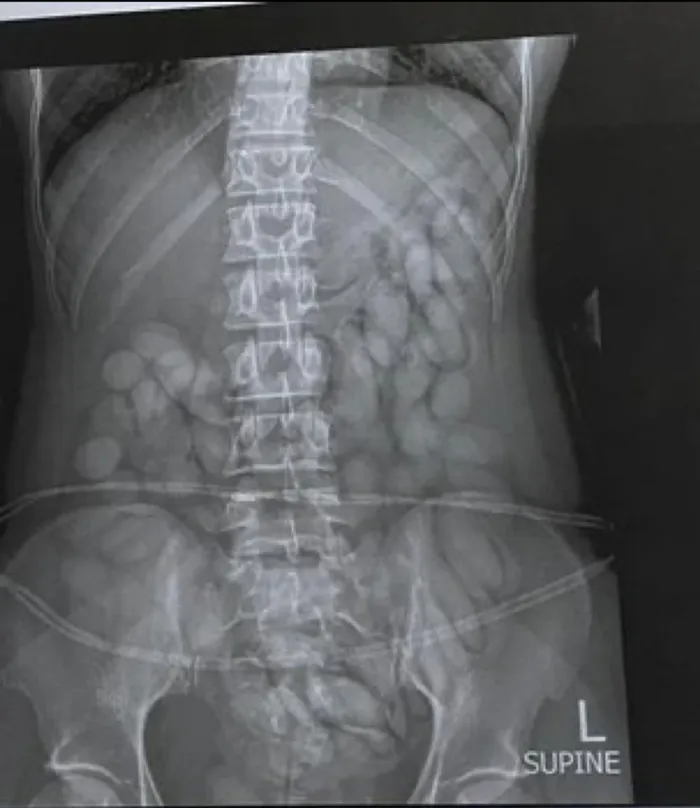

On Monday, a second medical examination/X-ray confirmed that all drugs had been removed from the Namibian drug mule’s body.

She was immediately arrested, taken to a local hospital where a medical X-ray confirmed and detected foreign objects in her stomach. The process to release the suspected drugs from her body, continued until late Sunday evening.

She first released more than 60 bullets of suspected cocaine. She was under police guard.